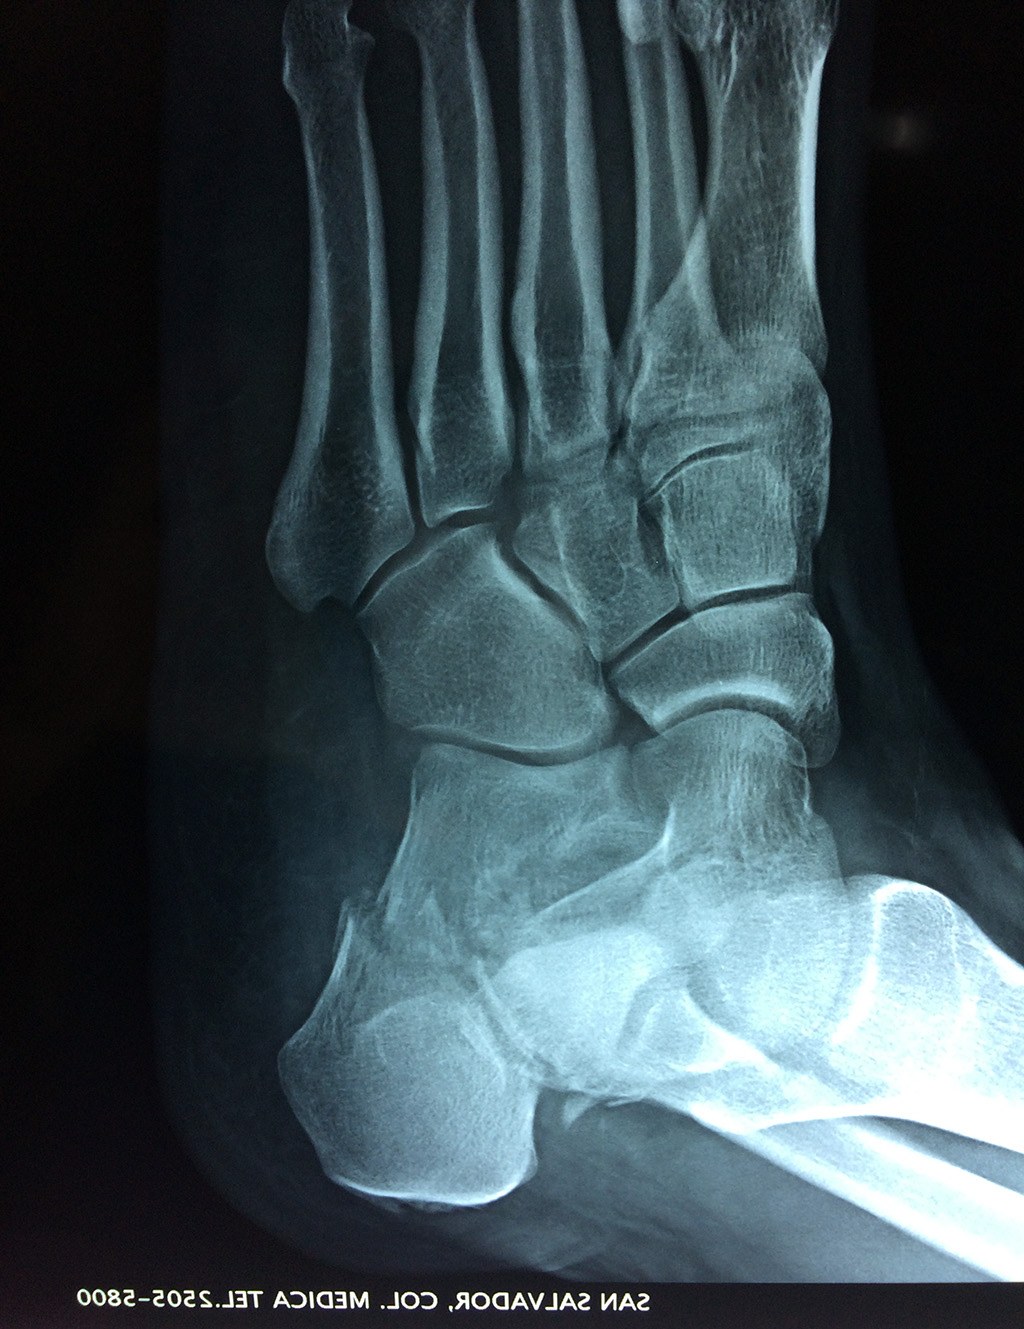

Este hueso constituye el talón del pie. Se encuentra en la parte inferior de la primera fila del tarso. Se articula con el astrágalo por arriba y con el cuboides por delante. Constituye el primer punto de apoyo del pie durante la marcha, situándose en una de las zonas peor irrigadas del cuerpo y protegido plantarmente por la almohadilla plantar de tejido adiposo, con función amortiguadora.

En su cara posterior recibe la inserción del tendón más plantar, implicada en diversas enfermedades como la fascitis o el espolón calcáneo. La posición del calcáneo en relación al astrágalo (articulación subastragalina) y al suelo determinan la posición de retropié en varo, en valgo o neutra.

Los retropiés varos y sobre todo, los retropiés valgos, son responsables de distintas enfermedades del aparato locomotor y contribuyen a que aparezcan alteraciones de la marcha normal fisiológica, con consecuencias clínicas importantes (dolor, sobrecargas, aplanamiento, fatiga muscular, juanetes, etc.) tanto a nivel de pie como a nivel del miembro inferior.

De todo esto se deriva que su posicionamiento espacial es muy importante para contribuir a una marcha correcta y a la salud del resto del conjunto articular del pie.